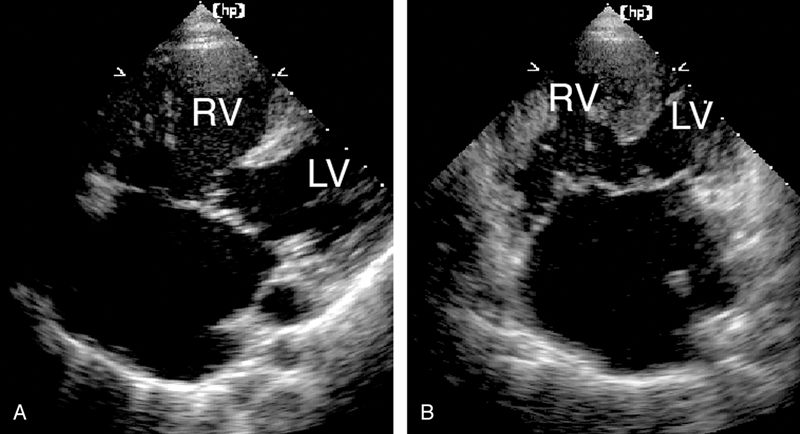

فحوصات تشخيصية لبعض امراض القلب والشرايين التاجية